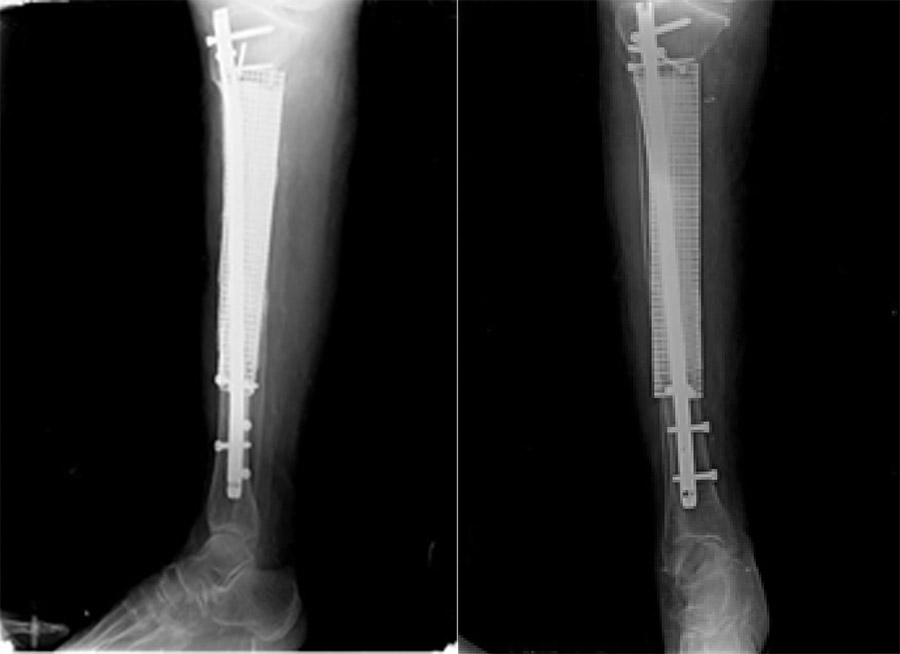

Post-surgery: The X-ray shows that the tumorous portion of the bone was removed, the resulting cavity was filled with titanium mesh and bone cement, and titanium nails were applied.